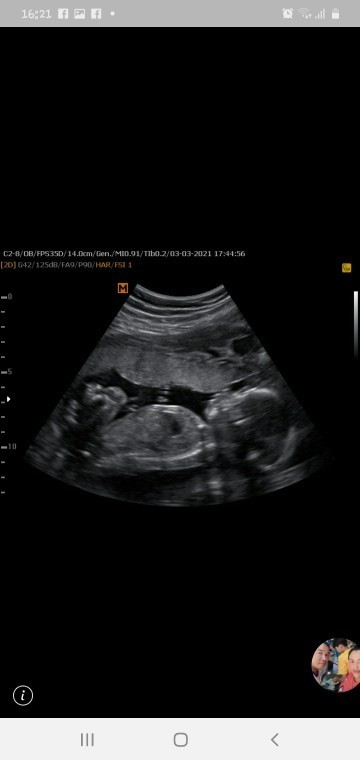

26 week ค่ะ

ญ ค่ะ

19วีค